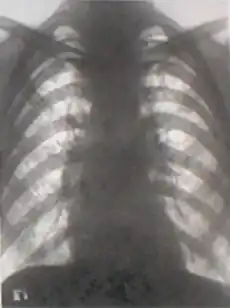

- No tipo longilíneo, indivíduos altos, magros, com uma distância púbis-pé superior à distância púbis-vértice da cabeça, tórax estreito, ombros estreitos, o coração adopta uma posição mais vertical tendo na radiografia torácica o aspeto chamado de "coração em gota". A ponta cardíaca desce abaixo do 5º espaço intercostal, mais central que a linha médio-clavicular e o impulso apical é por vezes sentido próximo do apêndice xifoide esternal.